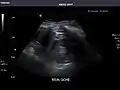

Kidneys: Right and left kidneys measure 11.5 cm and 12 cm in length respectively. No hydronephrosis. Small left lower pole kidney cyst.

Left kidney